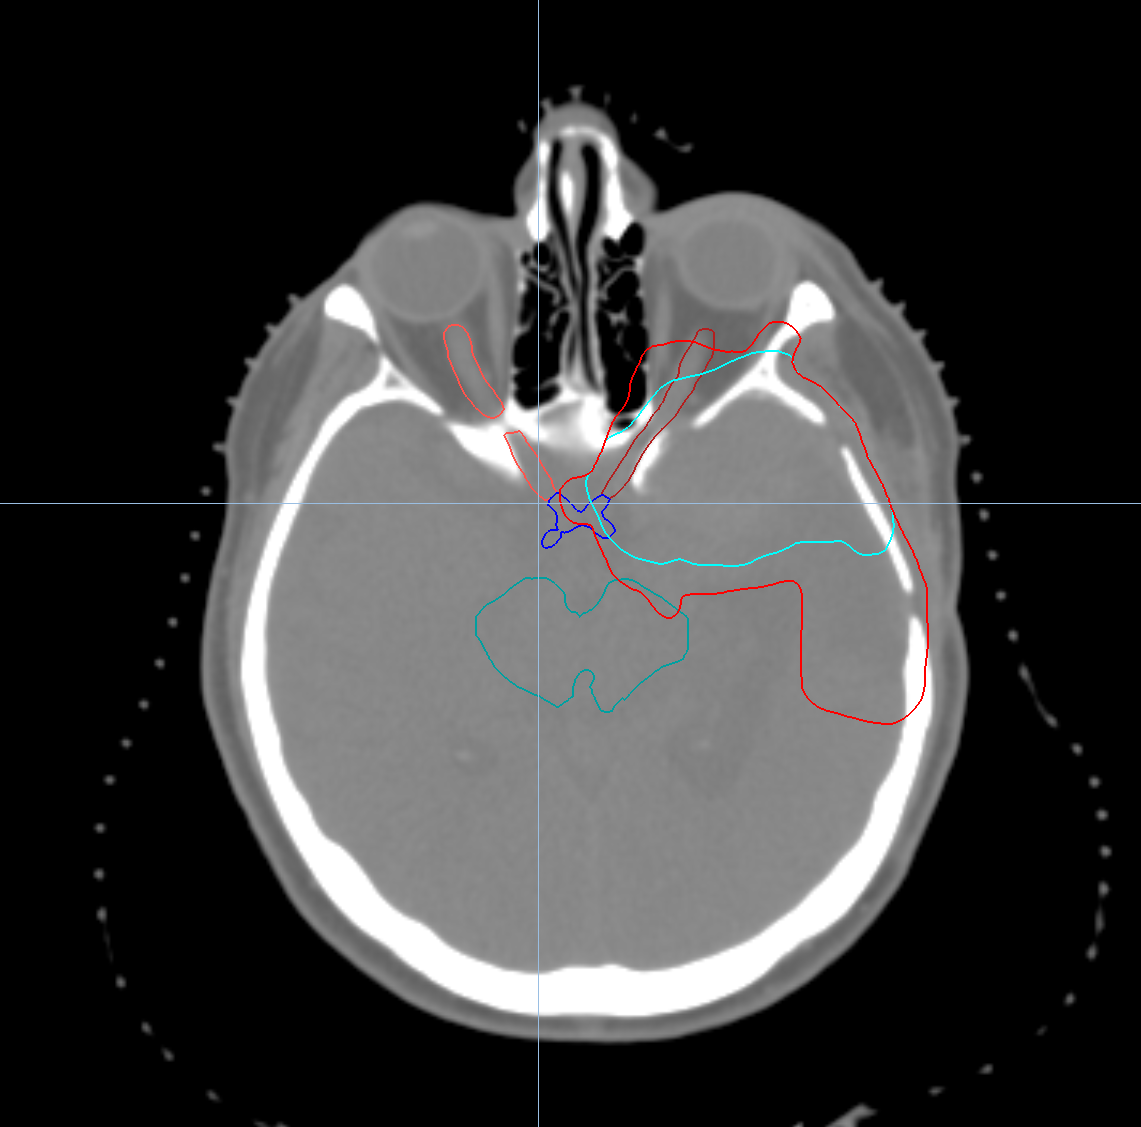

< View All Plan Studies RADIXACT SYSTEM Left Breast with Deep Inspiration Breath Hold Case History AGE: 76-year-oldGENDER: Male Medical History Immidiate tolerance: Grade II dermatitis with eyelid edema, Grade I conjunctivitis resolved with Sterdex Diagnosis: Squamous cell carcinoma of the right lower eyelid Planning CT Images Treatment Plan Images